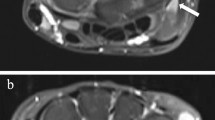

Proximal carpal row. a, b Coronal T1-weighted turbo spin-echo MR image in a 13-year-old boy (a) shows a large bony depression in the scaphoid bone (arrow). A 4-year follow-up (b) the depression is still seen but is less pronounced. New bony depressions are seen on the surface of the lunate and triquetral bones (arrowheads). c Coronal water-selective (coronal volumetric steady-state spoiled gradient echo) cartilage sequence shows that both old and new depressions are covered with cartilage

Depressions (arrowhead) in the lunate bone. a, b Coronal T1-weighted turbo spin-echo MRI in a 14-year-old boy (a). At 4-year follow-up MRI (b) the depression appears more irregular. c, d Coronal water-selective (coronal volumetric steady-state spoiled gradient echo) cartilage sequence at 4-year follow-up. Sagittal reconstruction (c) and coronal image (d) show intermediate signal on the articular side of the depression, which was therefore classified as not covered. The sagittal reconstruction (c) locates this depression to the dorsal side of the lunate